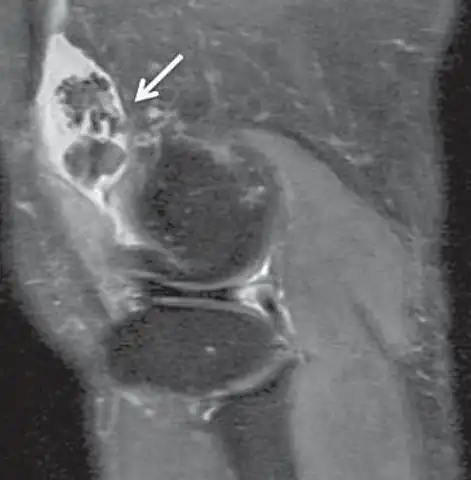

| Effective T2 or "T2-star" | T2* | Spoiled gradient recalled echo (GRE) with a long echo time and small flip angle[11] | Low signal from hemosiderin deposits (pictured) and hemorrhages.[11] | ![]() | |